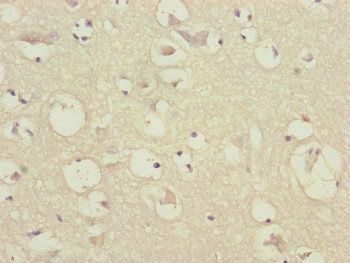

−FGF2 Antibody [orb411605]

IF, IHC, WB

Human, Mouse, Rat

Rabbit

Polyclonal

Unconjugated

200 μl, 100 μl, 50 μl, 30 μl